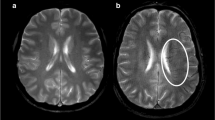

Table 2 provides clinical and radiological findings according to the status of cerebral collaterals. In patients with a high increase in K2, there was a trend for a higher rate of hemorrhagic transformation (17/51 vs 8/50, p = 0.07). Figure 3 presents examples of K2 in patients with good and poor collaterals.

Correlation of K2 to maps at admission and pre-thrombectomy digital subtraction findings. Upper panel: a representative case of a 58-year-old male patient presenting with an acute sylvian ischemic stroke on DWI (A, B). The symptom onset was 105 min, and the admission NIHSS score was 16. The K2 map (C) revealed increased BBB permeability within the infarct. Pre-thrombectomy digital subtraction arteriography (D) demonstrated occlusion of the M1 segment of the middle cerebral artery with no visible collaterals to the ischemic site, indicating a poor collateral status. Lower panel: an illustrative case of a 64-year-old female patient presenting with an acute sylvian ischemic stroke on DWI (E, F). The symptom onset was 92 min, and the admission NIHSS score was 19. The K2 map (G) did not show a significant increase in BBB permeability within the infarct core (E, F). Pre-thrombectomy digital subtraction arteriography (D) revealed an occlusion of the M1 segment of the middle cerebral artery with collaterals exhibiting slow but complete angiographic blood flow to the ischemic bed by the late venous phase, thus indicating good collaterals (H)